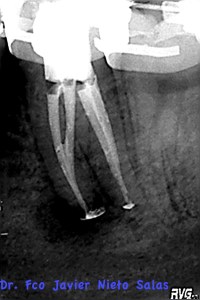

Usamos la técnica de ola continua de calor descrita por Buchanan y el backfilling se hizo con gutapercha inyectada.

Se citó a revisión a los nueve meses, no presentaba sintomatología y los signos claros de evolución positiva.